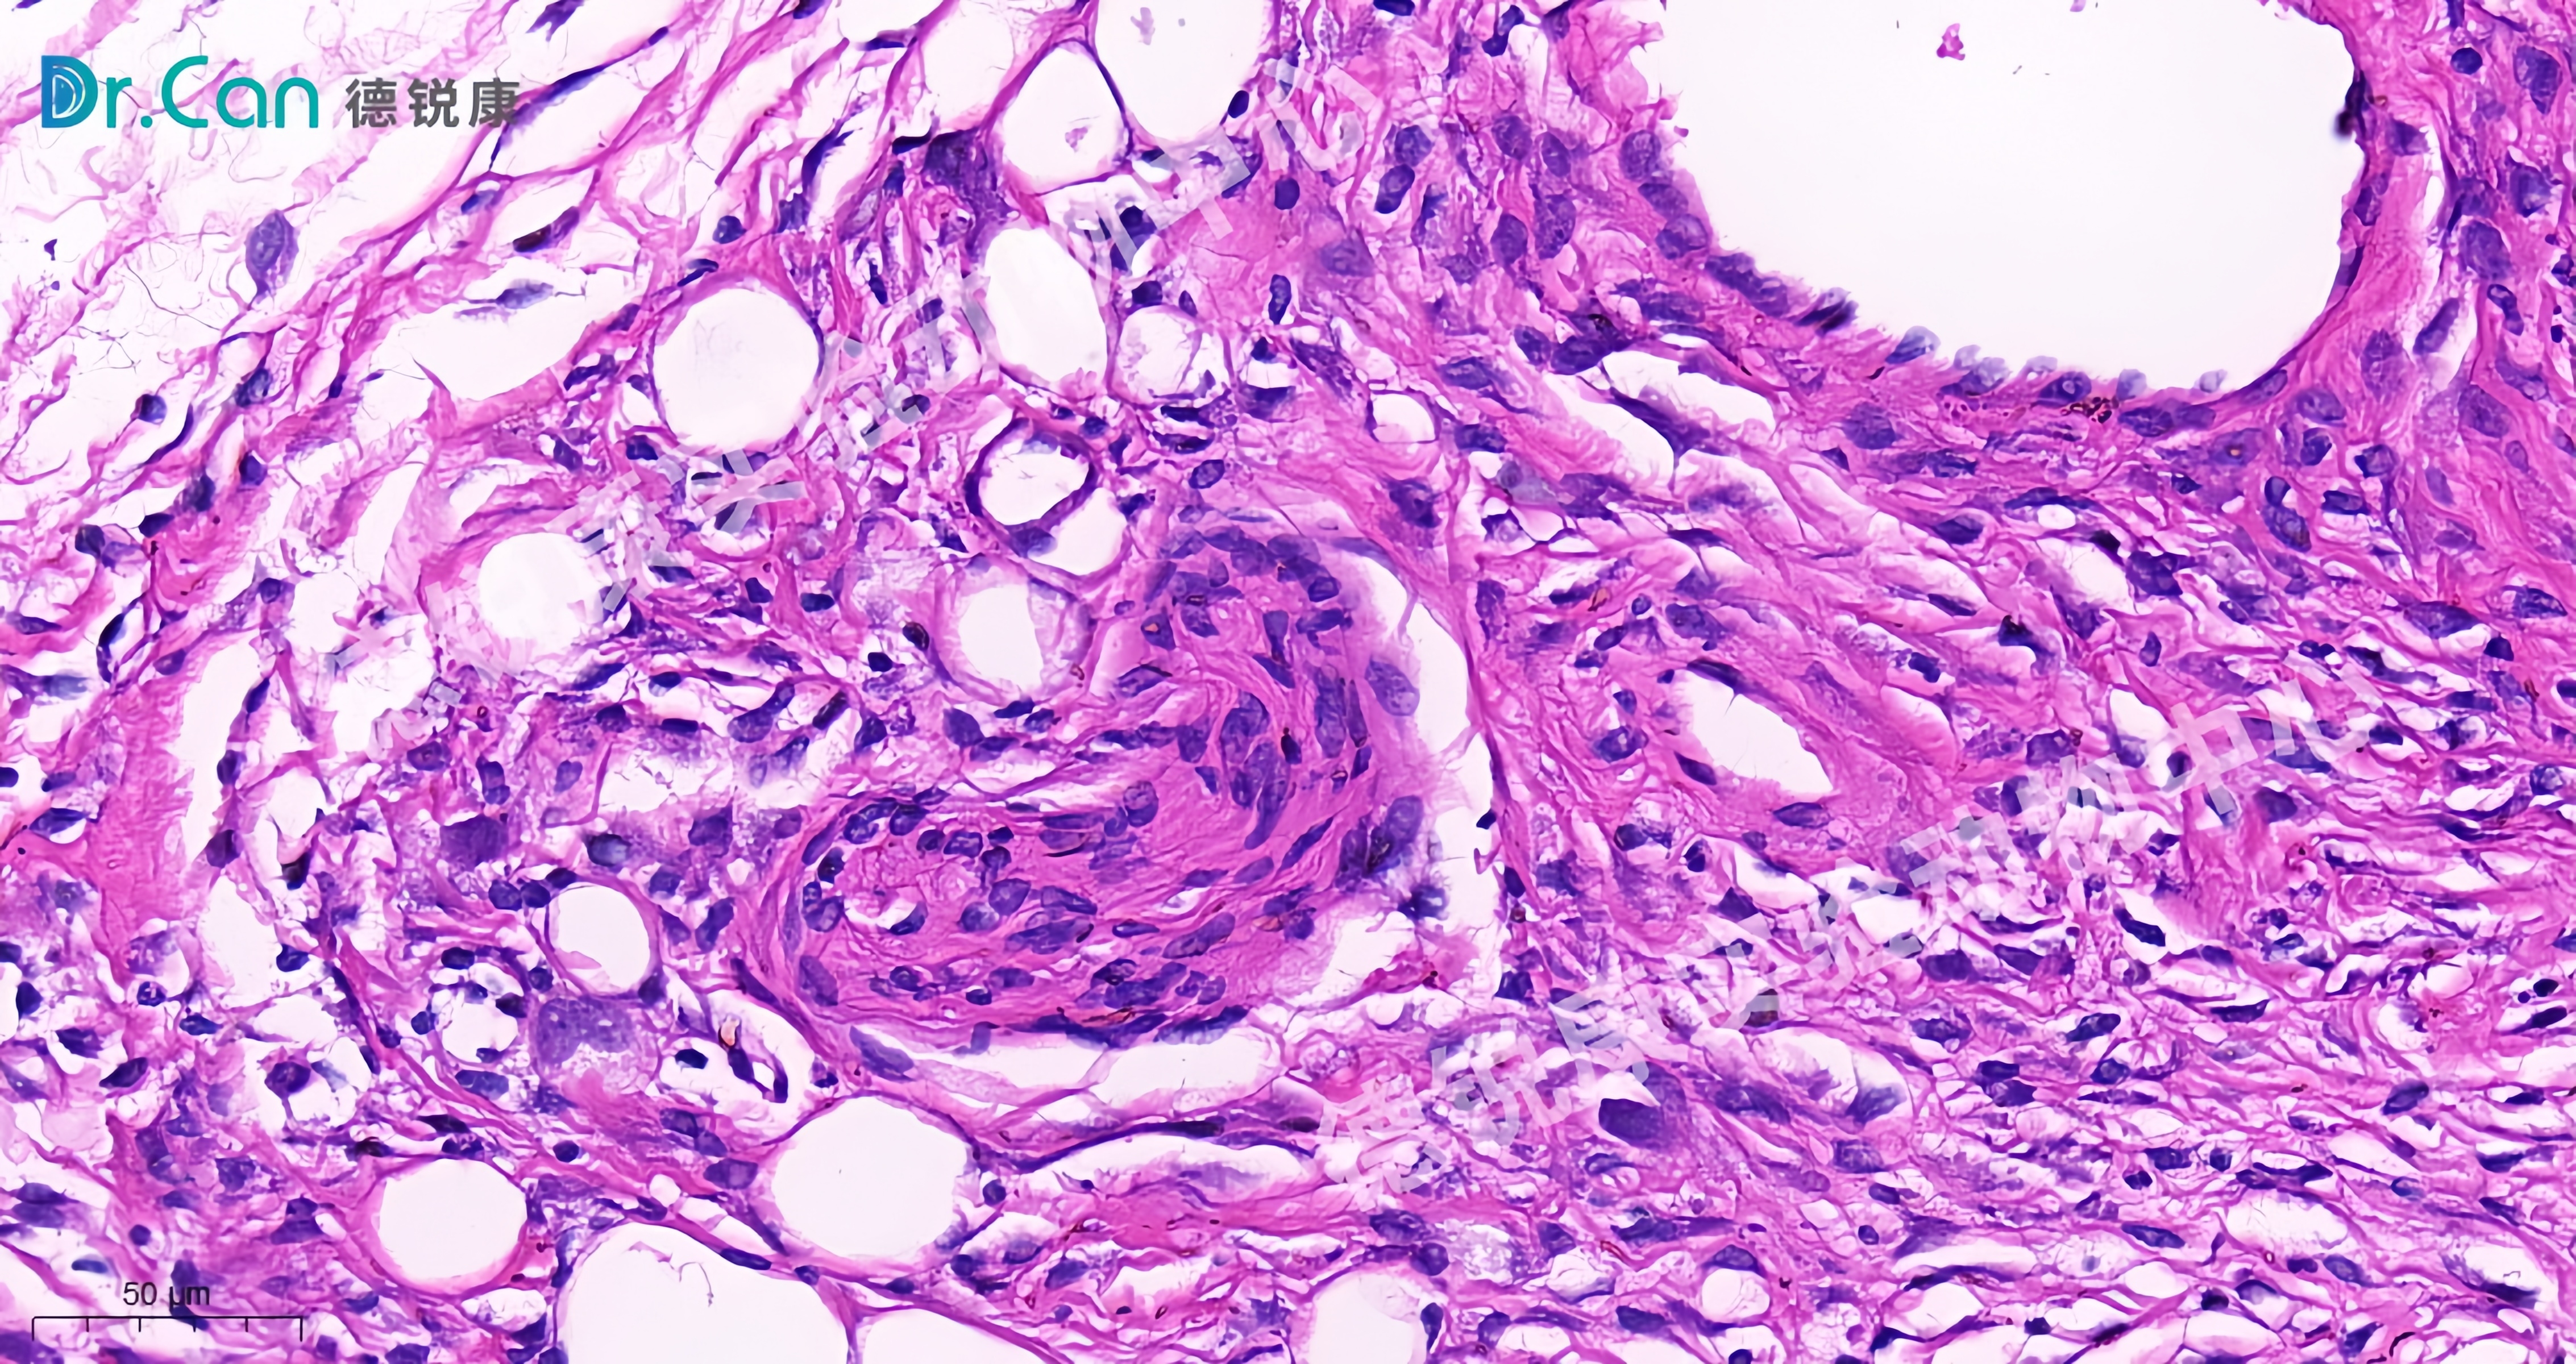

来自瘢痕细胞的玫瑰跟爱,你看。就连细胞都在告诉你 即使世界偶有磕碰,别怕,生命,永远爱你如初